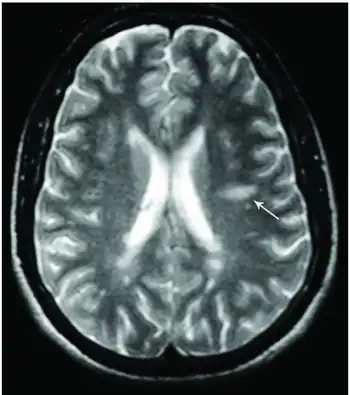

This morphologic appearance was named Dawson's fingers by Charles Lumsden, after the Scottish pathologist James Walker Dawson,[31] who first defined the condition in 1916.

Dawson's fingers

"Dawson's fingers" is the name for the lesions around the ventricle-based brain veins[32][33] of patients with multiple sclerosis and antiMOG associated encephalomyelitis[34]

Though once thought to be specific of MS, it is known not to be the case.[35]

The condition is thought to be the result of inflammation or mechanical damage by blood pressure[30] around long axis of medular veins.

Dawson's fingers spread along, and from, large periventricular collecting veins, and are attributed to perivenular inflammation.[36]

Lesions far away from these veins are known as Steiner's splashes.[30]